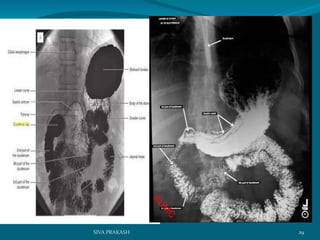

The pattern of the mucosal lining of the first part of the duodenum is different

from the other parts. longitudinal pattern of the mucosa of the first part of the

duodenum forming what is known as the duodenal cap This pattern is very

similar to that of thepylorus of the stomach This pattern changes to a

more flecked appearence in the distal duodenum

30SIVA PRAKASH

31SIVA PRAKASH